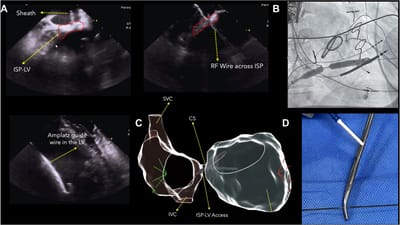

El Dr. Luis Quininir se ha convertido en pionero en Latinoamérica al realizar por primera vez de manera exitosa un innovador procedimiento de electrofisiología cardíaca, ampliando las fronteras del tratamiento de arritmias complejas. Este logro posiciona a Chile y al sur del país a la vanguardia regional, reafirmando el compromiso del Dr. Quininir con la excelencia clínica, la innovación y el desarrollo de la cardiología moderna. Un avance histórico que abre nuevas posibilidades terapéuticas para pacientes con arritmias complejas en la región.